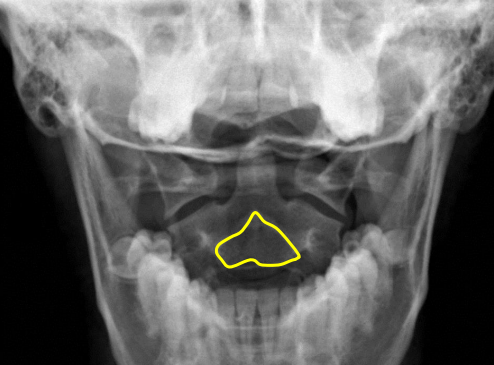

Mandible

Hyoid bone

Mitchel marker

Occipital condyle

C1 anterior tubercle

C1 posterior arch

Odontoid process

Atlanto-Dental interspace

C1 lateral masses

Mastoid process